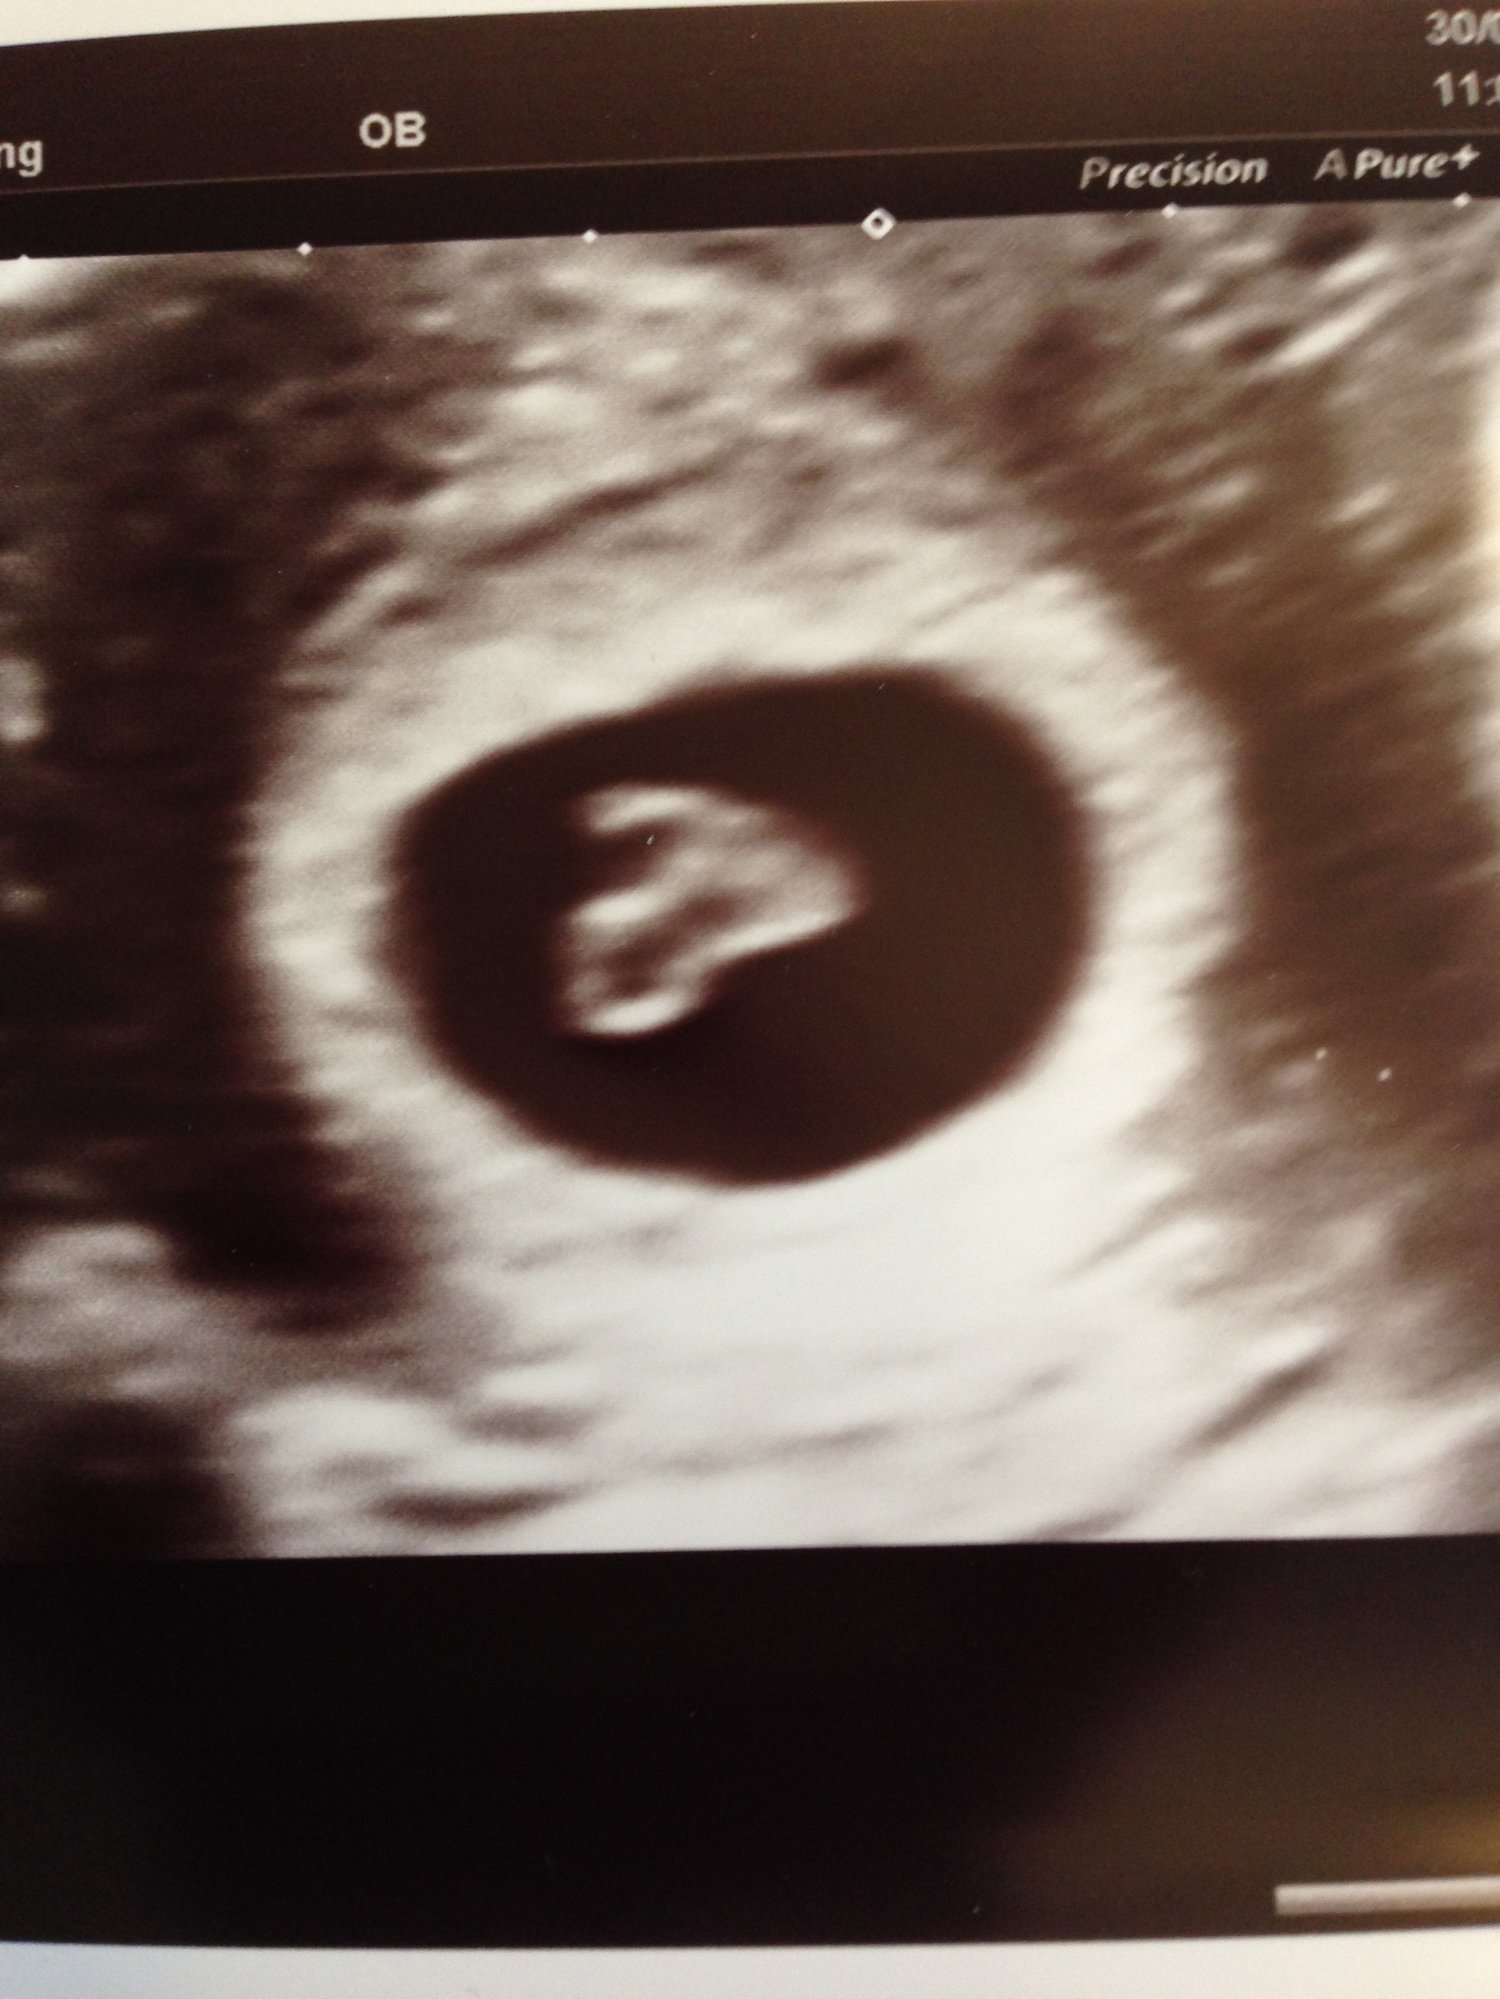

• Drs. standard practice to do an ultrasound at 8 weeks to confirm due date, and then a pap smear at 10 weeks.  I was excited for the ultrasound we got the see the baby, his ( projecting :)) little head and hear his heartbeat!  My official due date is Feb 2, but by measurements it looks more like Jan. 31, however the Dr. won't officially change the due date unless it's off by over 10 days between size and  Date of last menstral period.  So not excited for next weeks pap smear though :(